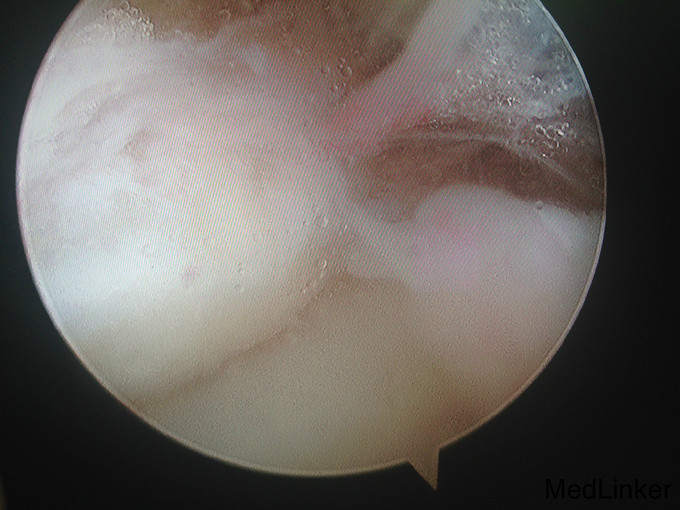

左踝扭伤后肿胀疼痛伴活动受限半年

查体:左腓肠肌萎缩,左踝轻度肿胀。左踝关节ROM较对侧降低,以背伸活动受限最明显。距腓前韧带处未及明显压痛。左踝内、外侧关节间隙压痛(+)。ADT(-),外侧应力试验(-)。左下肢肌张力正常、感觉正常。 辅检:MRI示“左踝关节积液”

诊断:左踝关节创伤性滑膜炎 治疗:左踝关节镜下滑膜清理、胫骨前缘成形

随访:患者术后即刻踝关节活动度恢复正常,2周恢复正常行走。 讨论:踝关节扭伤很常见,扭伤后会发生各种各样的情况。此患者扭伤后继发了滑膜炎,并伤及了关节软骨。这种情况应进行关节镜手术治疗。此外,核磁共振对关节疾患的诊断也是有限的,关节镜才是黄金标准。